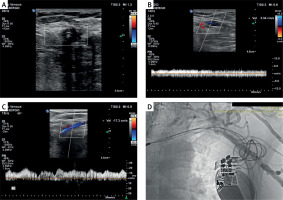

A specialist with at least 10 years of Doppler USG experience routinely performed US examinations on all patients in the supine position using a USG device (Philips EPIQ 7, Philips Health Care, Bothell, WA, USA) and a 12-5 MHz high-resolution linear probe. Both upper extremities of the patients were evaluated bilaterally with venous Doppler USG. To this end, brachial, axillary, subclavian, and jugular vein structures were firstly evaluated in B-mode. The probe was positioned to avoid venous compression, and lumen width, flow direction with color Doppler, and flow pattern with spectral Doppler were assessed. Consequently, complete loss of flow in at least three different regions of the subclavian vein was deemed to indicate a preliminary diagnosis of SVO (Figure 1 A). Antegrade continuous flow pattern in the ipsilateral and contralateral axillary veins, presence of respirophasic flow pattern, and axillary vein flow velocity were evaluated (Figures 1 B, C, respectively). All venous Doppler USG images were acquired using the device software. Images were evaluated by two different radiologists, and if consensus was not reached, a third radiologist’s opinion was obtained.

Figure 1

A – Doppler USG image of flow loss in the subclavian vein due to luminal obstruction with 3 pacemaker leads. B – Doppler USG image pertaining to the ipsilateral axillary vein featuring subclavian vein occlusion: i) disappearance of respirophasic flow, ii) decreased flow (3.34 cm/s) iii) antegrade continuous flow. C – Normal Doppler USG image pertaining to the contralateral axillary vein of a patient with left subclavian vein occlusion; i) antegrade respirophasic flow pattern, ii) normal flow velocity (17.3 cm/s). D – Verification of the occlusion by Doppler USG in the left subclavian vein of the same patient with venography image

Venography procedure

Definitive diagnosis of SVO was made with venography on the day of CRT-D battery replacement in patients with a preliminary diagnosis of SVO by venous Doppler USG. To this end, a 1.3-gauge venous cannula was inserted into the ipsilateral antecubital vein and 20–30 ml of non-ionic, water-soluble contrast agent was prepared. A tourniquet was applied on the venous pathway before contrast agent injection. After contrast agent injection, the tourniquet was removed and then 20 ml saline was infused. Subsequently, complete cineangiography of the axillary vein, subclavian vein, and brachiocephalic trunk was performed in the anterior posterior projection. The images were evaluated by an experienced electrophysiologist. Abrupt cessation of contrast flow in the subclavian vein and visualization of the collateral system were deemed to indicate a definitive diagnosis of SVO (Figure 1 D).